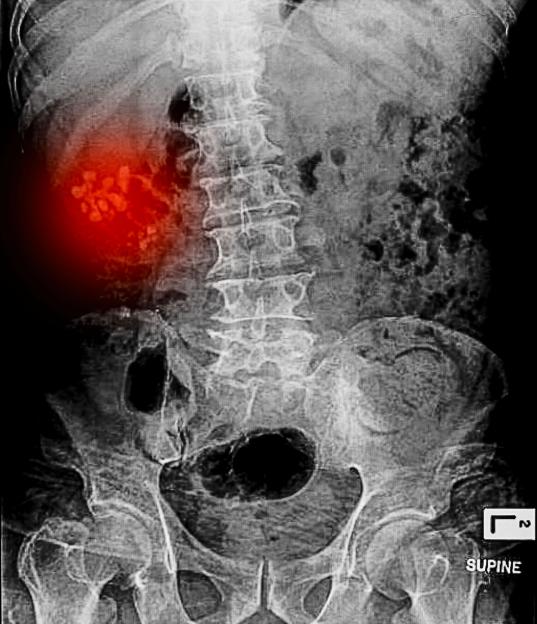

Q) I’M a man who recently had an , which found kidney stones on either side.

Can you advise remedies for me while I wait for a referral to hospital?

One reader had an ultrasound which revealed kidney stonesCredit: Getty

A) I’m sorry to hear that. Did you have symptoms?

can be completely painless if they are small and remain in the kidney.

When a stone travels down the ureter (the tube that connects the kidney to the bladder) and gets stuck, this can cause severe pain known as renal colic.